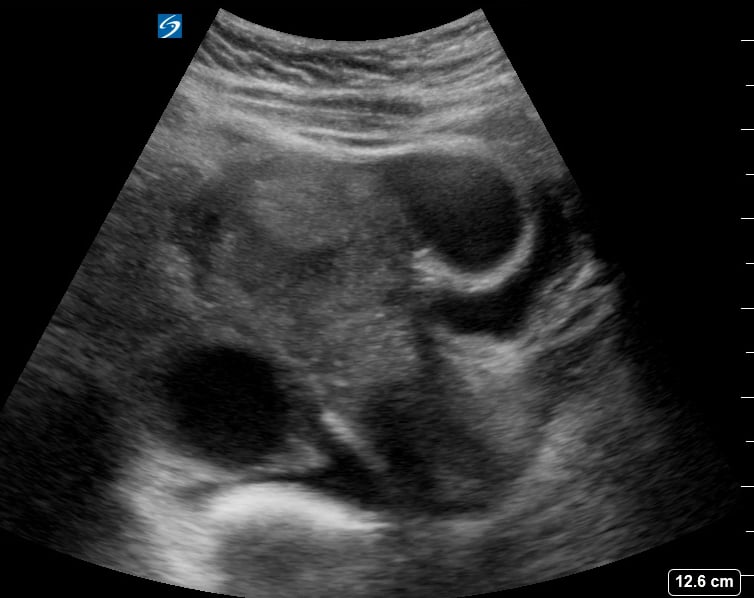

Ultrasound is the primary diagnostic tool for ectopic pregnancies, allowing visualization of the gestational sac outside the uterine cavity. Medical professionals rely on sonographic findings, alongside clinical symptoms and hCG levels, to confirm the diagnosis and guide appropriate management, including medication or surgery.